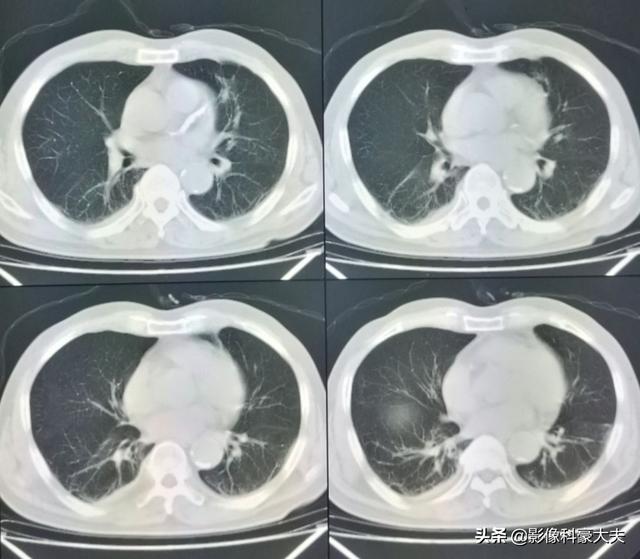

直近のCT検査の結果、原発巣はかなり縮小しており、5年以上保菌したまま生きられたのは幸運だった!